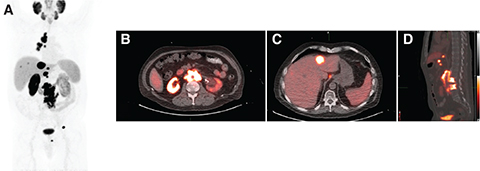

Post-therapy scintigraphy can be performed at a single time point after 177Lu-PSMA RLT administration or at multiple points in a serial fashion, typically ranging from 120 minutes to 8 days post-injection (Figure 3). Post-therapy scintigraphy can be performed by planar imaging or single photon emission computed tomography (SPECT). A significant disadvantage of planar imaging compared to SPECT/CT is its inaccuracy in distinguishing between overlapping areas of radiotracer uptake present in more than one organ, which most likely results in dose overestimation.

Fig 3

Figure 3. A 57-year-old male with mCRPC. A, 68Ga-PSMA PET-CT Maximum intensity projection (MIP) image shows widespread intensely PSMA avid osseous lesions in the axial and appendicular skeleton. B, Fused sagittal image showing multiple intensely PSMA avid sclerotic lesions in the spine. C, PSMA post-therapy emission planar images (anterior and posterior) acquired 7 days after the therapy show PSMA-avid osseous lesions in the axial and appendicular skeleton with a distribution similar to the PSMA PET/CT.